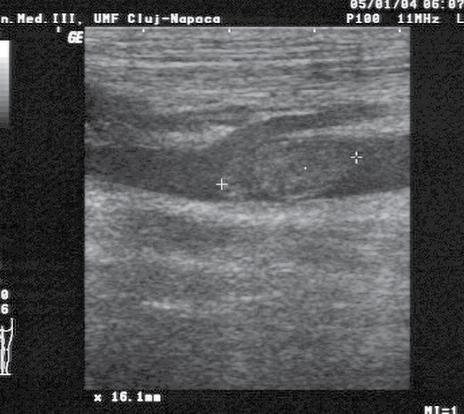

• identificarea sacului pericardic, a colecțiilor pericardice și impactul de tip tamponadă (fig.1) cu risc de activitate electrică fără puls – necesitatea pericardiocentezei într-un serviciu de cardiologie-chirurgie cardiovasculară;

Fig.1. Secțiune subxifoidiană. Colecție pericardică. Cavități cardiace drepte colabate. Ventricul stâng cavitate redusă

Fig.4. Secțiune intercostală dr. venă cavă inferioară